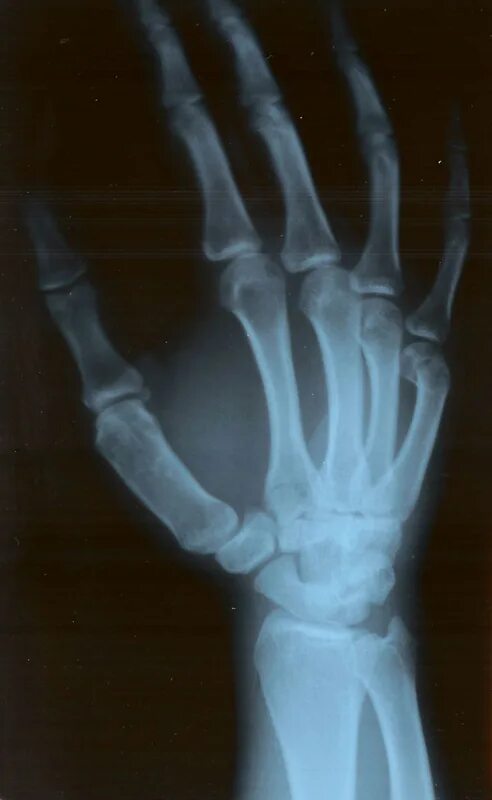

Перелом 3 пястной кости